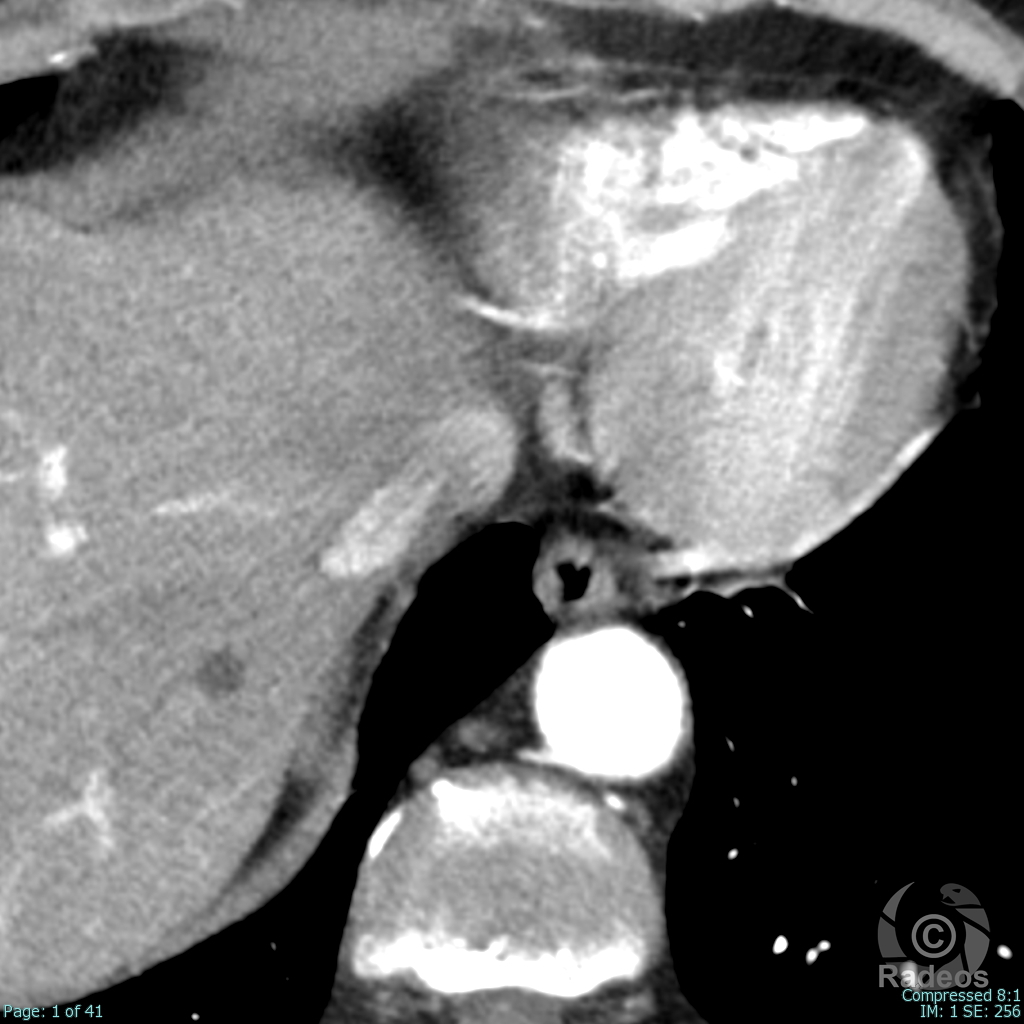

Aspect IRM d'une fibromatose profonde de la paroi abdominale. Découverte fortuite d'un angiome hépatique gauche.